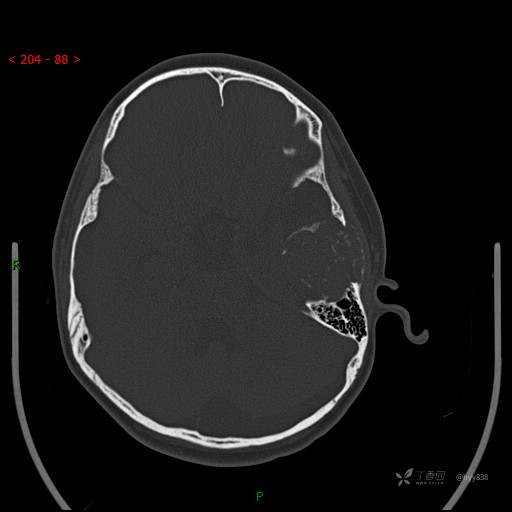

“典藏”病例分享。10岁儿童,头痛头晕一周余,CT、MRI 都有---结果公布~

简要病史:患者于一周前无明显诱因开始出现头痛头晕,无恶心呕吐,无肢体抽搐,无寒颤高热,无腹胀腹泻,无视力下降及视野缺损,上述症状休息后可稍缓解,未引起重视。 2天前患者头痛头晕不适加重,伴有恶心感,无呕吐,遂到当地人民医院行头颅CT检查示:左侧颞部占位性病变,今日家属为求进一步治疗,来我院门诊求治。门诊拟“左侧颞部占位性病变”收入我科。 患病以来,患者精神、饮食、睡眠尚欠佳,大小便如常,体力体重无明显变化。

临床诊断:左侧颞部占位

颅脑CT扫描